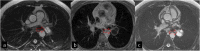

Hydatid cyst caused by the larval form of Echinococcus is a worldwide zoonosis. The lungs and liver are the most common sites involved. While the lung parenchyma is the most common site within the thorax, it may develop in any extrapulmonary region including the pleural cavity, fissures, mediastinum, heart, vascular structures, chest wall, and diaphragm. Imaging plays a pivotal role not only in the diagnosis of hydatid cyst, but also in the visualization of the extent of involvement and complications. The aim of this pictorial review was to comprehensively describe the imaging findings of thoracic hydatid cyst including pulmonary and very unusual extrapulmonary involvements. An outline is also given for the findings of complications and differential diagnosis of thoracic hydatid cyst.